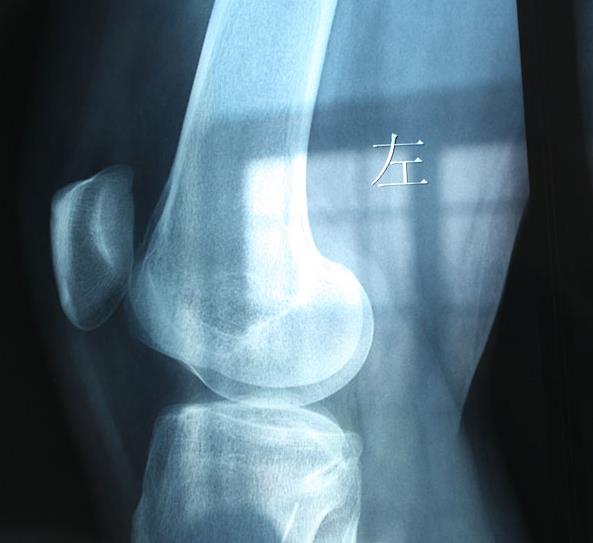

29日上午,在临沂市第四人民医院外一科病房,记者见到了王女士,她刚刚于7月28日做完手术。据了解,王女士是兰山区人,一周前她乘电动三轮车外出。行至市区某路段时,一私家车将王女士乘坐的电动三轮撞翻。随后王女士来到市第四人民医院拍片检查。但检查的结果让王女士感到很意外:骨骼等组织均没事,但X片却显示左膝关节外侧皮下有一个几厘米长、金属样的物体。王女士感到很奇怪,自己没有做过手术,也没有被扎过,体内怎么会有金属样的东西呢?于是王女士又重新拍了个片,结果和此前的一样。

这个金属样的物体到底是什么?“隔皮猜瓜”谁也弄不清楚,医生称必须做手术才能知晓。7月28日,王女士被推上手术台。参与手术的刘大夫发现,位于王女士左膝关节外侧皮下约1厘米处有一缝衣针。“缝衣针长约5厘米,在她体内已断成了两截,一截长4厘米,一截长1厘米。”刘大夫说,缝衣针被包在脂肪组织内,属于炎性包裹。刘大夫随后将缝衣针剥离取出。